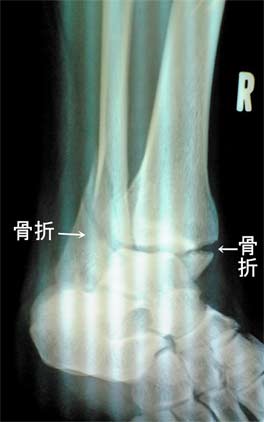

やっと当初の骨折レントゲン写真を撮らせていただきました。

懐かしく痛々しそうですが、あまり骨折の痛みは感じていなかったです。

これが正面から移したレントゲン写真です。

正面から見た内側(写真の右側)は、下側小さく折れている様子です。

外側(写真の左側)は、鋭く折れているのですが、この写真ではちょっと不明。

下側の骨も曲がってしまっているそうですが、素人には判りませんね(笑)